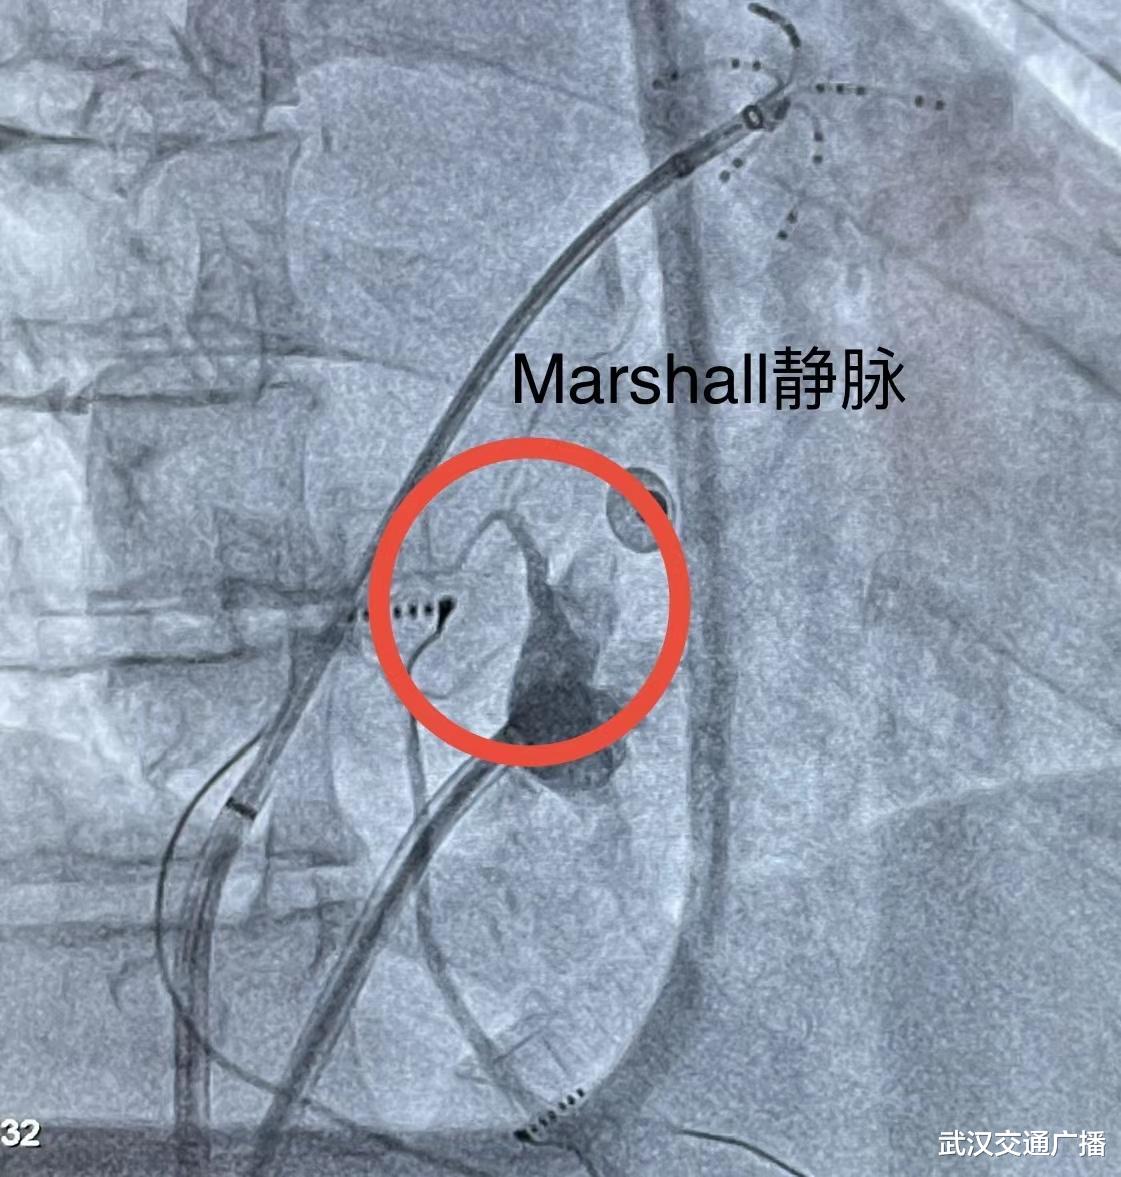

心血管内科主任刘涛接诊了梅爹爹 , 经心电图检查提示“心房扑动和心房颤动” , 心室率高达150次/分 。 刘涛主任仔细分析梅爹爹病情 , 详细评估后认为 , 患者既往已经做过两次房颤消融手术 , 现在又复发 , 结合梅爹爹本人情况 , 本次选择Marshall静脉无水酒精化学消融联合经典房颤射频消融是目前最好的治疗方案 。

经过充分术前准备 , 心血管内科主任刘涛带领团队在介入室为梅爹爹行Marshall静脉消融 , 术中 , 患者立即恢复窦性心律 , 操作过程中患者未感觉明显不适 , 无水酒精消融过程总共耗时15分钟 , 术后验证二尖瓣峡部彻底阻滞 , 未再诱发出任何类型的心律失常 , 手术非常成功 。

刘涛主任介绍 , 房颤是最常见的心律失常 , 房颤早发现、早治疗很重要 , 房颤病人缺血性卒中风险是正常人5倍 。 经导管途径进行Marshall静脉的无水酒精化学消融是房颤消融领域一个重大的技术创新 , 它融合了电生理和冠脉的手法和技术 。 通过这项创新技术 , 使持续性房颤、左房房扑和复发性房颤消融成功率提高15% , 还有效避免导管消融不彻底或者消融过度引发的心脏穿孔 , 减少导管消融的手术并发症 。